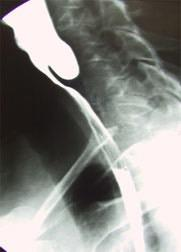

Zenkerโs Diverticulum

- Question: A 62- year- old male with dysphagia, halitosis and regurgitation of undigested food.

- Answer:

- A-What is the name of the test?

- Barium swallow

- B-What is the diagnosis?

- pharyngeal pouch or Zenkerโs Diverticulum

- C- Whatโs the treatment?

- Cricopharyngeal myotomy. (Botox) the issue of this is that we have to repeat the same thing after 4 months.

- Diverticulectomy (we can say surgical excision) more preferred due to less complications.